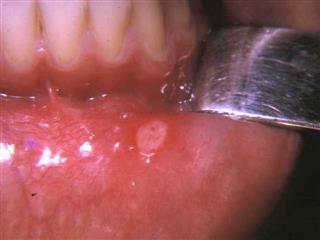

DES APHTOSES BUCCALES

Dans son livre « Homéopathie en Odonto-stomatologie » (1974), Jean MEURIS écrivait dans son chapitre sur « L’aphtose » :

« Alors que l’école officielle est pratiquement désarmée dans le traitement de l ‘aphtose, nous obtenons des guérisons définitives de cette affection récidivante, dès le moment où, selon la conception homéopathique, nous considérons et les phénomènes locaux et les signes généraux du terrain ».

Et bien nous partageons totalement cette opinion. Au cours de l’année 1969, nous avons eu personnellement un cas rebelle et c’était alors notre première prescription homéopathique dans un cas chronique. Le médicament de fond était THUYA. Et le succès a été éclatant, étonnant pour la patiente qui avait subi en vain toutes sortes de traitements classiques, encore plus étonnant pour le praticien néophyte en homéopathie. C’est ce cas précis qui a motivé notre thèse de doctorat en chirurgie dentaire en 1973. Et depuis nous avons suivi quelques dizaines de cas et nous pouvons corroborer l’affirmation de notre regretté confrère Jean MEURIS.

Dans ces cas d’aphtose buccale, comme dans les autres pathologies, la méthode homéopathique doit s’appliquer avec la même rigueur. Si le patient arrive à la consultation au moment d’une poussée aiguë, il faut noter tous les symptômes locaux qui se rapportent à cette poussée, y compris éventuellement les signes concomitants extra-buccaux. Ensuite dans une deuxième consultation, l’anamnèse, les signes de comportements, les signes ou symptômes généraux seront recherchés minutieusement et c’est sur l’ensemble que l’on proposera le traitement de fond. Pour un praticien exercé, le recours au répertoire n’est pas toujours nécessaire. Sinon, voici ce que propose le Répertoire de KENT :